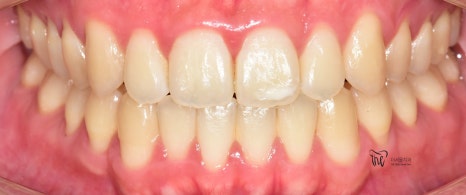

『덧니교정 치료 사례, 인비절라인 장치 사용』

정면 및 측면에서 봤을 때, 측절치의 후방위치에

따라서 반대교합 형태를 보여주고 있으면서

이 때문에 송곳니가 더 덧니처럼 보여지는 느낌을

받고 있는 모습을 볼 수 있습니다.

나아가, 하악의 전치부 쪽에도 총생 현상이

같이 관찰이 되면서 이런 비심미적인 요소들을

개선시키고 싶은 마음으로 더서울치과에

내원하셨던 분입니다.

치열이 많이 가지런하게 펴진 것을 볼 수 있고,